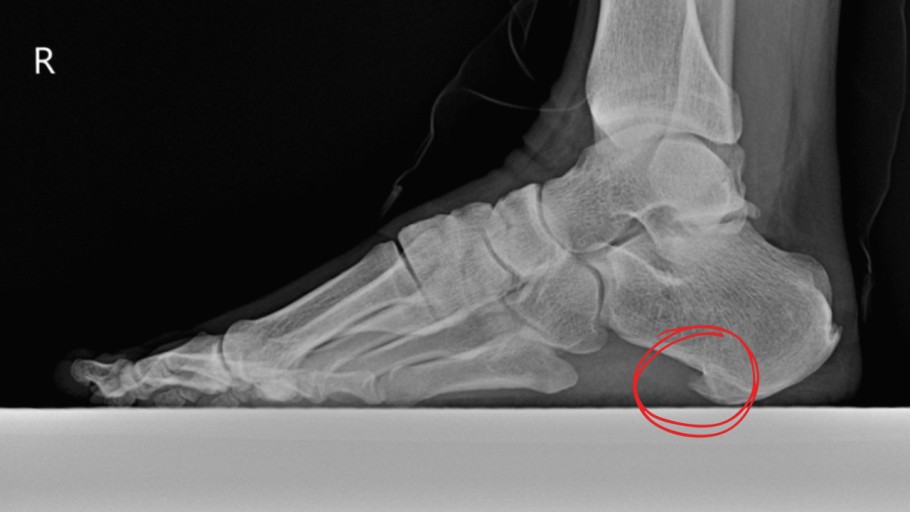

발바닥에 있는 족저근막에 손상이 발생해서 염증과 통증을 일으키는 질환인데요. 흔히 발뒤꿈치 통증을 일으키는 대표적인 질환입니다. 평균 발병 연령은 45세 정도이고, 여성이 남자보다 2배 정도 많이 발생해요. 족저근막은 발뒤꿈치 뼈에서 발바닥 앞쪽으로 이어진 두꺼운 섬유 띠인데요. 이는 발바닥의 탄력과 아치 모양을 지속시켜 줍니다. 발을 들어 올릴 수 있게 해 주며 발에 가해지는 충격을 흡수하기 그리하여 보행 시 매우 주요한 역할을 해요.